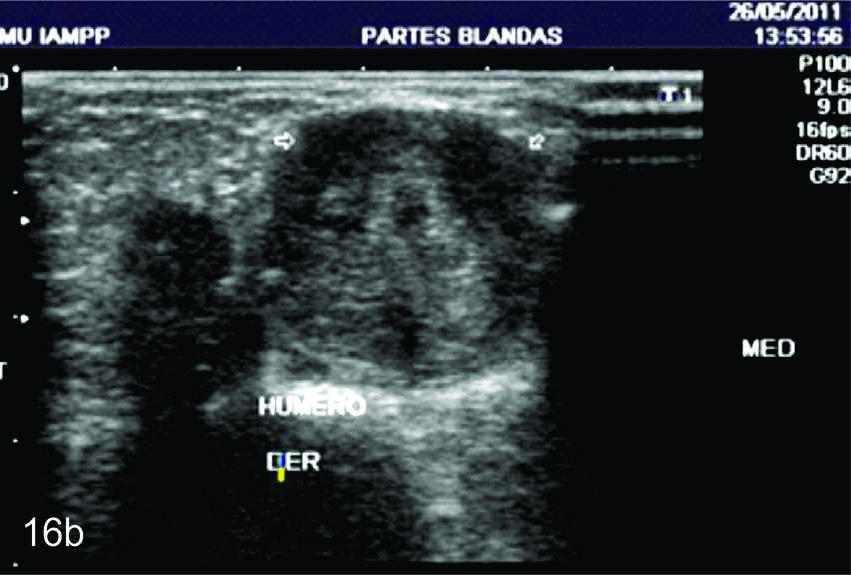

Figura 16

Tumor del nervio radial a nivel del brazo derecho.

A- Se observa un corte longitudinal del nervio radial proximal a la lesión (flechas blancas abiertas), se observa como el mismo se encuentra levemente engrosado y como se continúa con la masa en estudio (flecha amarilla). B- Corte transversal del mismo paciente en donde se identifica un tumor homogéneo ligeramente hipoecogénico y bien delimitado de los planos musculares adyacentes (flechas blancas abiertas).